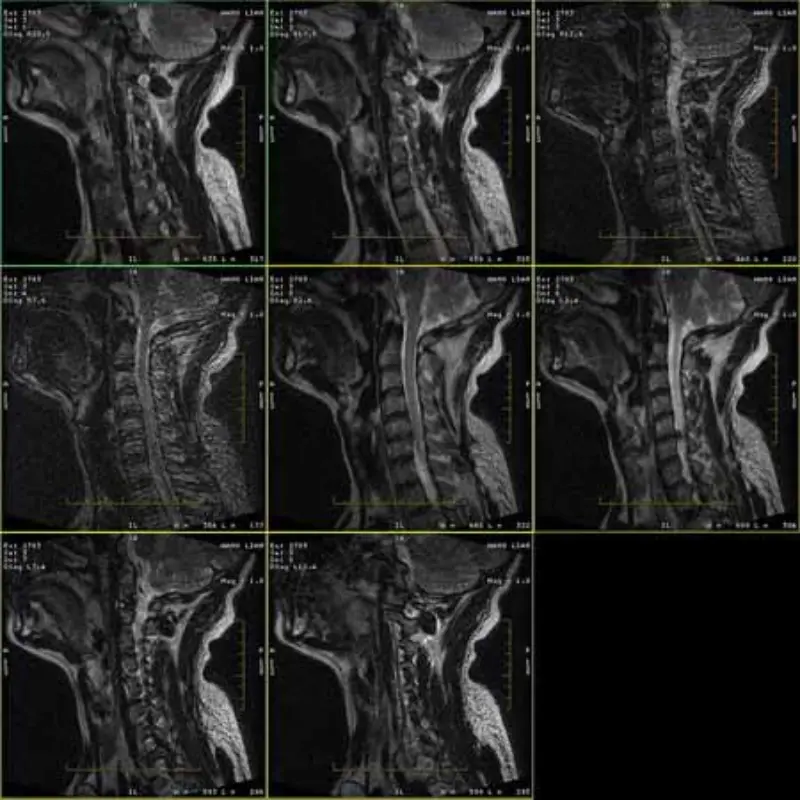

Las imágenes de los protocolos FRFSE y GRE tienen imágenes fantasma y, a veces, aparecen imágenes con SNR baja en una serie. Pero las imágenes del protocolo SE son normales.

Por favor mire adjuntar imágenes.